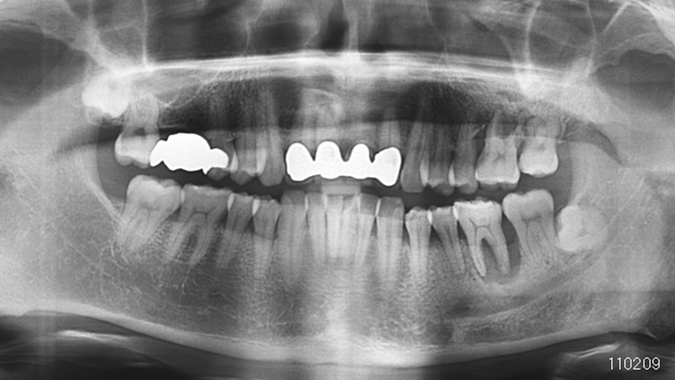

Clinical case: Bone growth in deepest thread of 8.0mm AnyRidge fixture

- Courtesy of Dr. Kwang Bum Park -

Clinical case: Bone filling into the bottom of deepest thread at 8.0mm AnyRidge fixture

Keywords

AnyRidge, Knifethread ,extraction socket, ,initial stability ,Allograft, ,osseointegratio ,Dr. Kwang Bum Park, , Mandibular, Single replacement, AnyRidge, Mega-oss,

Products used

Implant system-AnyRidge, Regeneration-Mega-Oss